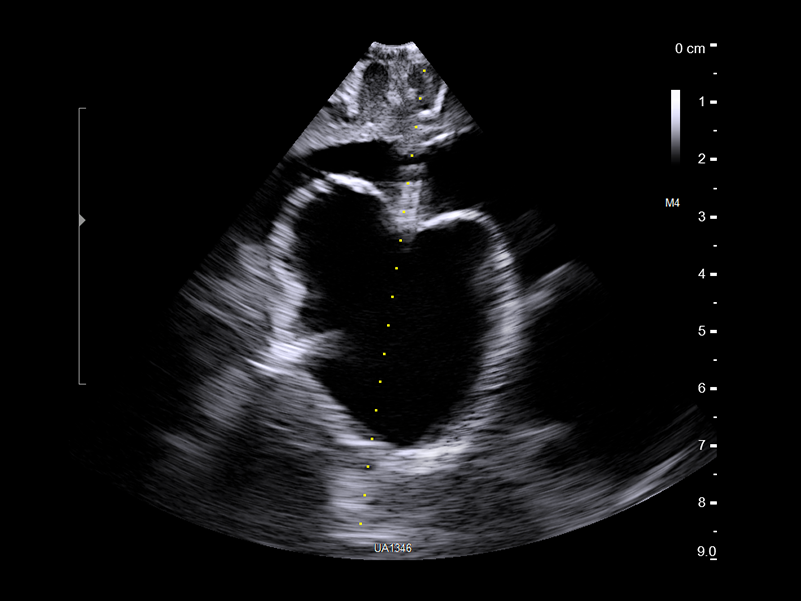

REAL-TIME VISUALIZATION HAS NEVER LOOKED THIS GOOD

- Enhanced Visualization: Improved algorithms for greater details around lesion borders, and automated high-resolution image settings.

Surgical Visualization and Guidance’s active imaging solutions combined with Brainlab Navigation can be a powerful tool to provide critical information that helps neurosurgeons navigate procedures.

Brainlab Ultrasound Navigation Software provides updated images for navigation and enables real-time overlay of ultrasound imaging on preoperative MRI/CT, providing immediate information about brain shift. The digital transmission ensures no loss of ultrasound image quality.